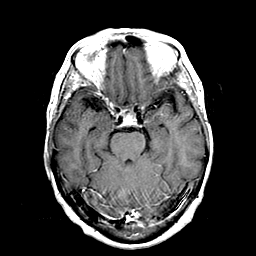

Metastatic Adenocarcinoma of the Colon: T1-weighted MR -- Slice #9

[Home][Help][Clinical] Slice 9